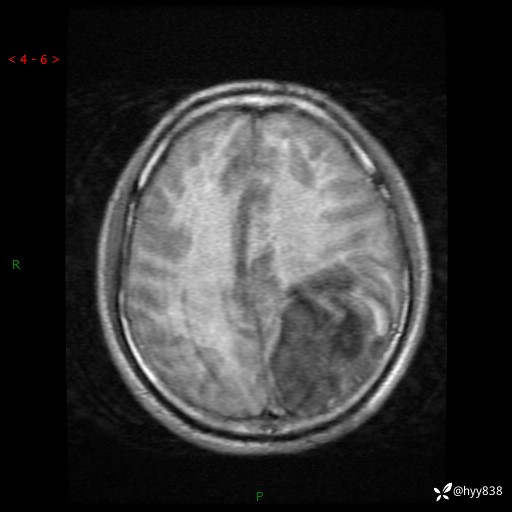

病例年轻小伙,头痛伴呕吐半年,渐进性加重1月。疑难病例,第一次见--结果公布~

性别:男

年龄:21岁

简要病史:头痛伴呕吐半年,渐进性加重1月

颅脑MRI平扫+增强